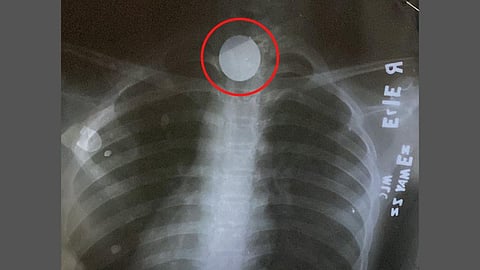

नाशिक : खेळता-खेळता १२ वर्षीय मुलीने दहा रुपयांचे नाणे (Coin) गिळले. मात्र तिला वेळीच नाशिकच्या (Nashik) जिल्हा रुग्णालयात दाखल करण्यात आल्यावर येथील कान, नाक आणि घसा तज्ज्ञांनी तत्काळ दुर्बिणीद्वारे शस्रक्रिया करुन तिच्या घशातील नाणे बाहेर काढले. ज्योती प्रकाश गवळी असे या मुलीचे नाव आहे. (Doctors Withdraw the coin stuck in the throat; Doctors give life to 12-year-old girl)

दोन दिवसांपूर्वी खेळतांना १० रुपयांचे नाणे तिच्या घश्यात अडकले होते. त्यामुळे तिला जेवतांना आणि श्वास घेताना त्रास जाणवू लागला. ज्योतीला नाशिक जिल्हा रुग्णालयातील आपत्कालीन विभागात दाखल करुन एक्स-रे तपासणी करण्यात आली. त्यानंतर पूर्ण भुल देऊन दुर्बिणीतून शस्त्रक्रिया करून हे दहा रुपयांचे नाणे यशस्वीपणे बाहेर काढण्यात डॉक्टरांना यश आले.